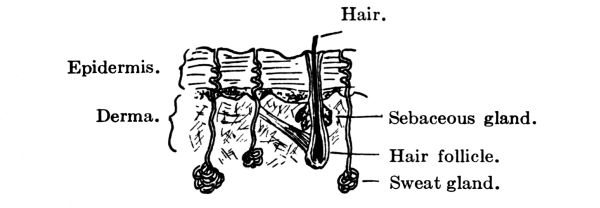

The whole exterior surface of the body is covered by the skin, an excreting and absorbing organ, which serves as a protection to the parts beneath and is also the organ of touch. It has two layers, a superficial and a deep. The superficial layer, the epidermis or cuticle, is composed wholly of epithelial cells, of which the deepest layer is columnar and moulded upon the papillary layer of the derma, while the intermediate layers are more rounded and the surface ones flat. The deepest layer also contains the skin pigment, which causes the variation in shade between the Indian, the negro, and the white man. Below the epidermis, which is chiefly protective, is the tough, elastic, and flexible tissue of the derma or true skin, in which are vested most of the activities of the skin. Its surface is covered with papillæ, which are more numerous in the more sensitive parts. Each papilla contains one or more capillary loops and one or more nerve fibers, while some terminate in an oval body known as a tactile corpuscle. Beneath the papillæ is the reticular layer, composed of interlacing bands of fibrous tissue and containing blood-vessels, lymphatics, and nerves, as well as unstriped muscle fibers where hair is present.

Fig. 11.—Vertical section of skin.

The hairs also, which occur all over the body, except on the palms of the hands and the soles of the feet, are a modification of the epithelium. Each hair has a bulbous root springing from an involution in the epidermis and derma called the hair follicle, into which one or two sebaceous glands empty. It is raised by involuntary muscle fibers and grows by constant additions to the surface by which it is attached. This growth seems, however, to be limited, and when its term [Pg 41] is reached the hair falls out and is replaced by another. The horny epithelial cells that go to form the hair contain the pigment that gives it its color.

Like the hairs, the sebaceous glands are situated in all parts of the body except the palms of the hands and the soles of the feet. They lie in the papillary layer and empty into the hair follicles, except occasionally, when they empty directly upon the surface of the skin. They secrete an oily substance, sebum, the débris resulting from the degeneration of the epithelial cells of the gland itself, which serves to keep the hair glossy and the skin soft and flexible. [Pg 42]

The sweat glands, on the other hand, are more frequent on the palms and soles and though sometimes found in the derma are usually situated lower down in the subcutaneous cellular tissue. They are least numerous on the back and neck. Coiled up in the lower layers of the skin, they discharge the sweat through a spiral excretory duct upon its free surface.